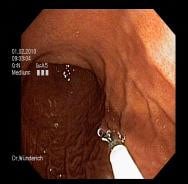

Magenspiegelung (Gastroskopie)

Die Magenspiegelung dient dazu krankhafte Veränderungen im Bereich der Speiseröhre, des Magens und des Zwölffingerdarms festzustellen. So können zum Beispiel Entzündungen, Geschwüre und Tumore diagnostiziert werden. Während der Untersuchung ist es möglich Gewebeproben zu entnehmen und z.B. Krebsvorstufen wie Polypen zu entfernen. In Ihrer Wertigkeit ist die Magenspiegelung durch keine andere Untersuchung zu ersetzen.

Die Magenspiegelung wird mit einem Endoskop durchgeführt. Hierbei handelt es sich um ein flexibles, schlauchartiges Instrument, an dessen Spitze eine miniaturisierte Optik angebracht ist. Zur Untersuchung legen Sie sich auf die linke Seite und atmen ruhig und gleichmäßig. Das etwa fingerdicke Endoskop (9,5mm) wird dann durch einen Beißring, den Sie zwischen den Zähnen tragen, über den Mund in die Speiseröhre und durch den Magen bis in den Zwölffingerdarm vorgeschoben.